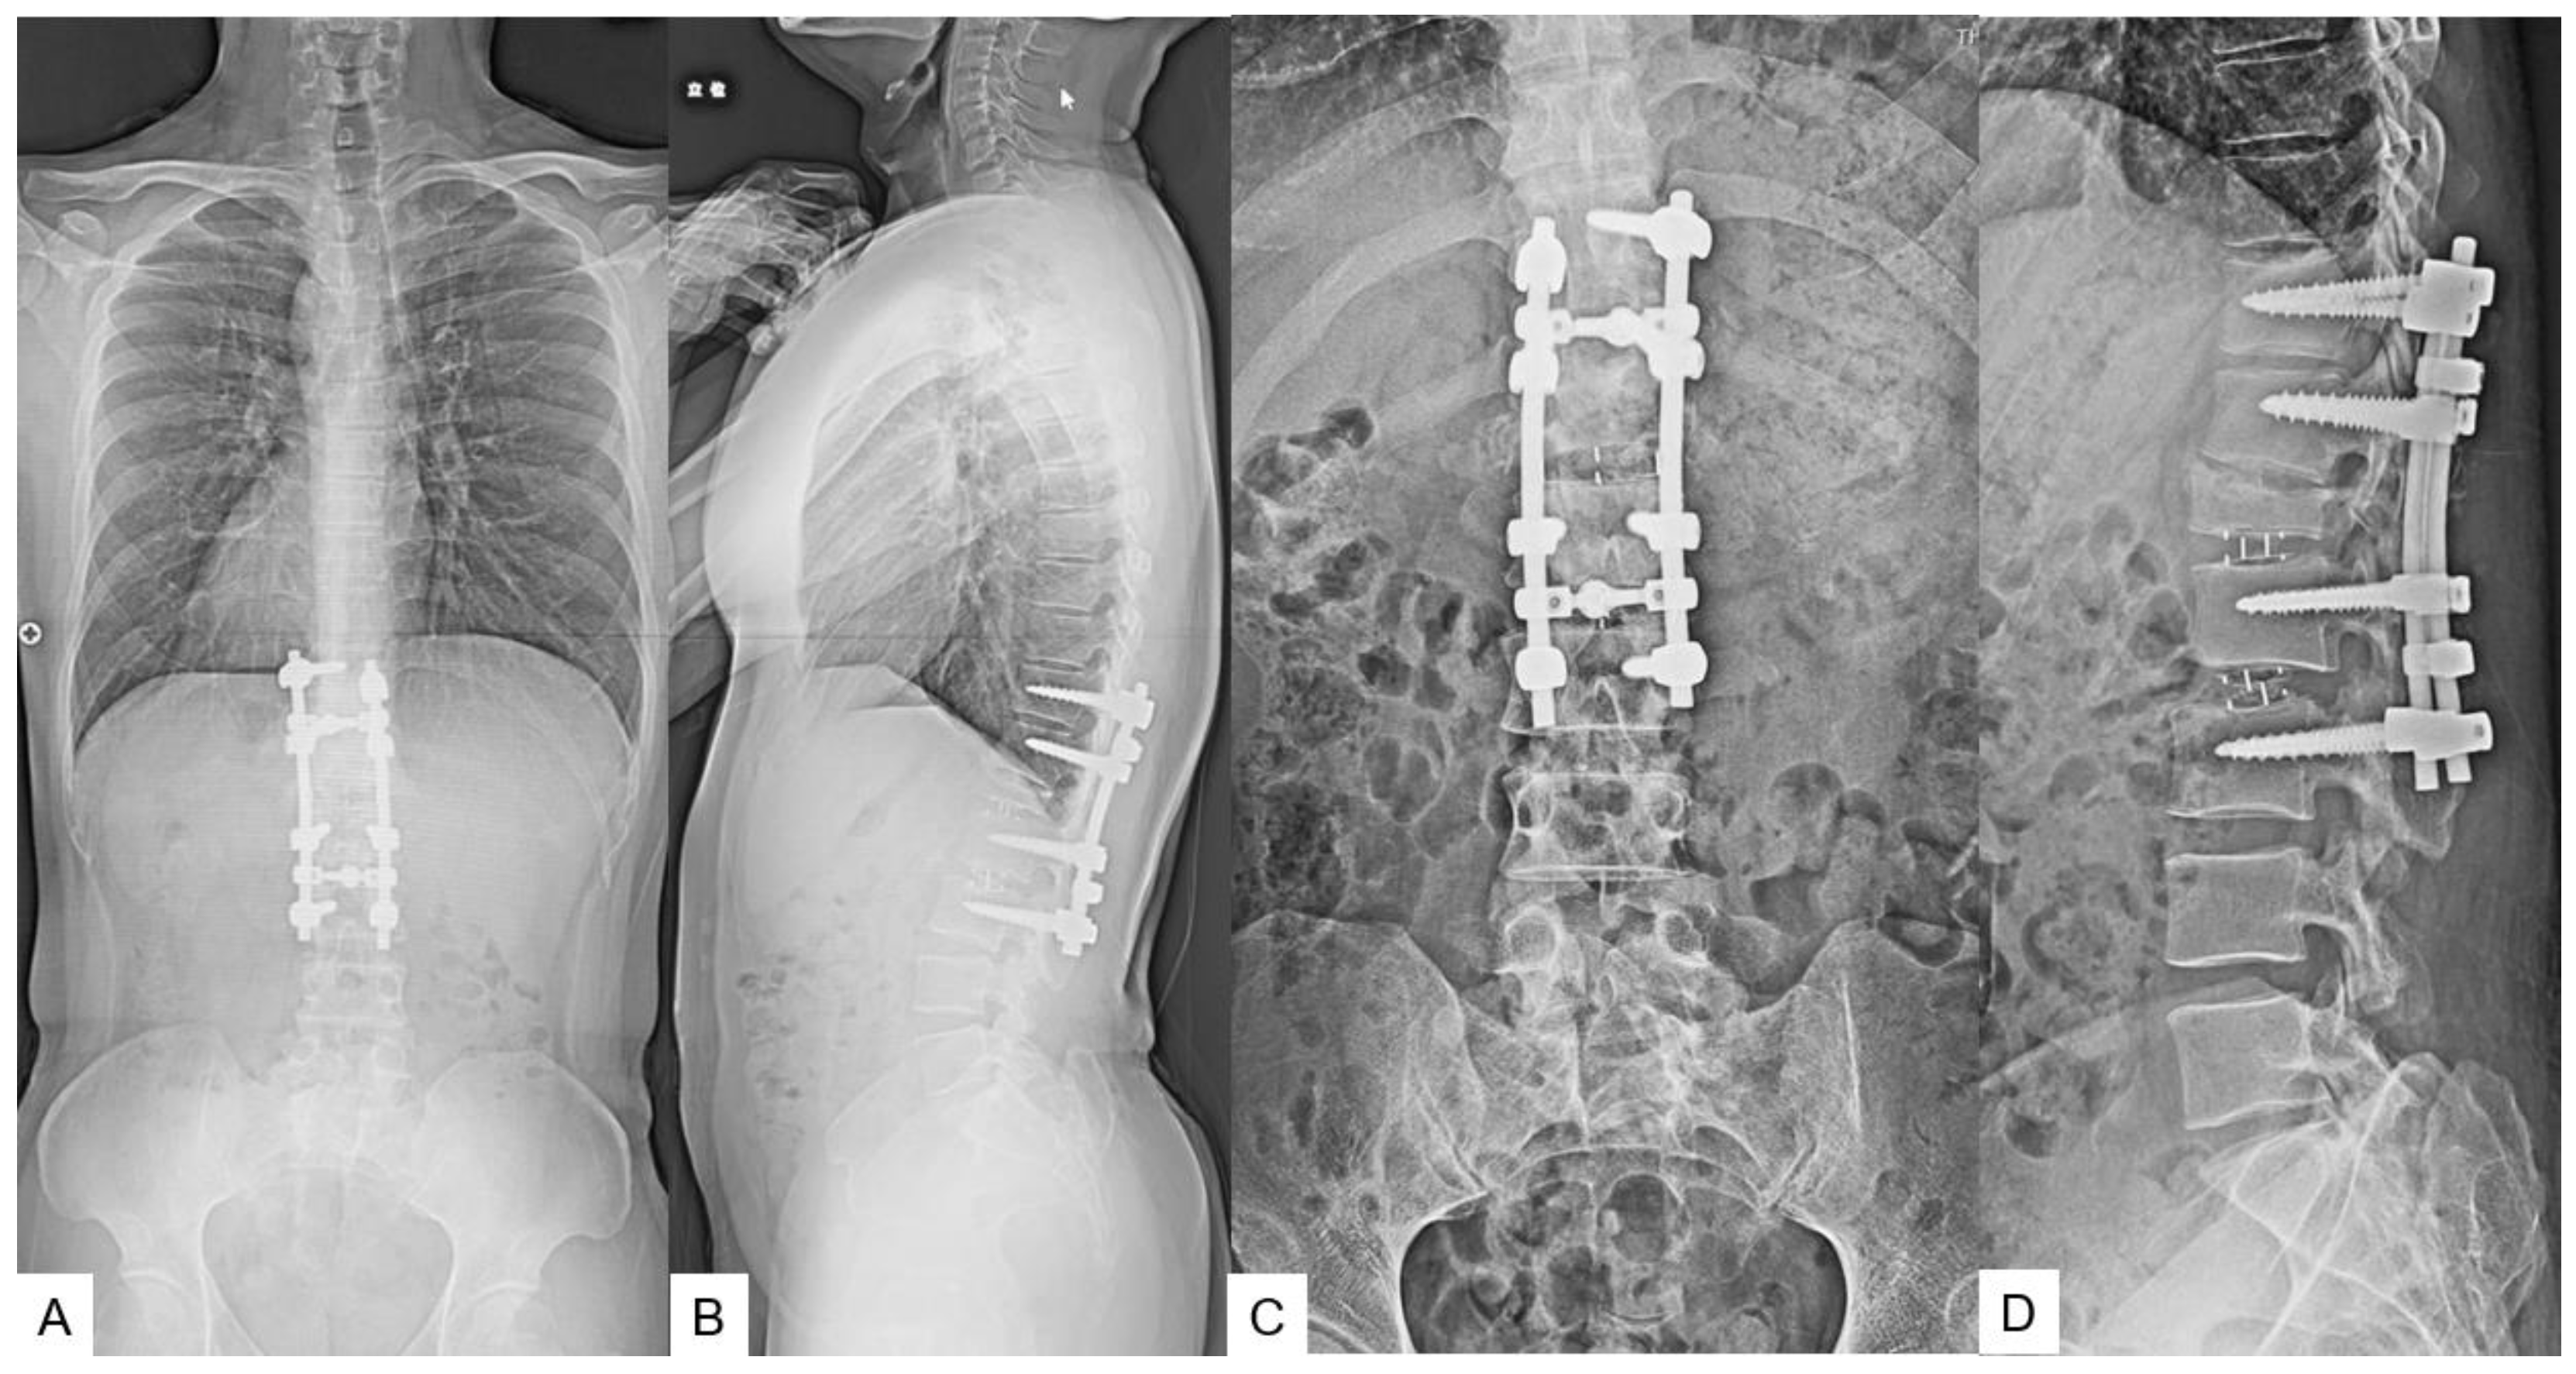

2.5. Postoperative imagings.